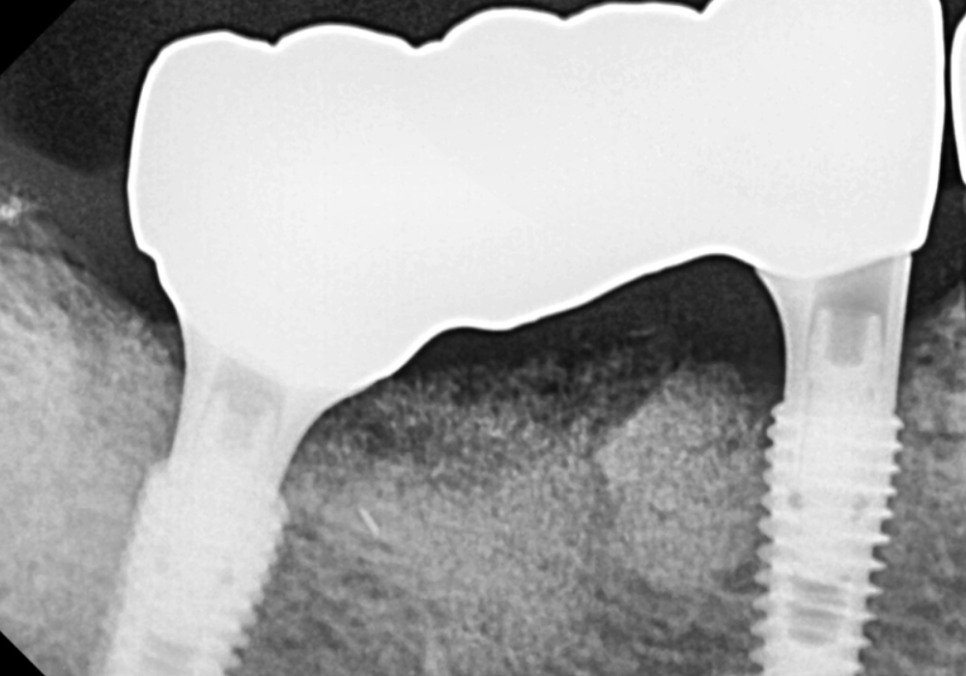

그로부터 약 3개월의 시간이 흘렀습니다.

임플란트 뿌리가 잇몸뼈와

얼마나 튼튼하게 하나가 되었는지

ISQ(고정 수치)로 꼼꼼히 확인한 후,

드디어 최종 보철물을 올려드렸습니다.

260203

예전에 접착제로만 고정하는

임플란트 방식(cement type)과는 다르게

임플란트를 더 오래 유지하실 수 있도록

'SCRP 타입'으로 보철물을 제작해 드렸는데요.

환자분들께는 조금 생소할 수 있는 이 방식,

왜 중요할까요?

'SCRP 방식'이란?

오래된 임플란트, 흔들림과 통증

쉽게 말해, 나사로 고정하는 방식과

치과용 접착제로 고정하는 방식의

장점만을 합친 스마트한 보철 형태입니다.

보철물 가운데에

작은 구멍(Screw hole)이 있는 것이 특징이죠.